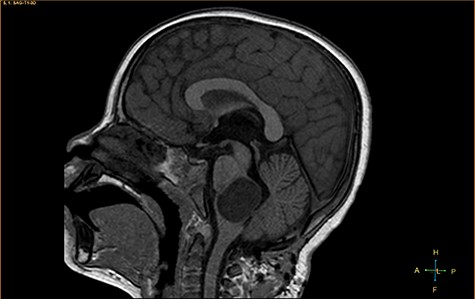

A 3-year-old male, who suffered from a sudden, tonic–clonic seizure, followed by a short period of unconsciousness, was instantly transported to Children’s Hospital 2. The patient’s medical history was normal. No neurological deficits were detected during the clinical assessment, and laboratory tests and electroencephalography were within acceptable ranges. The clinician performed a brain magnetic resonance imaging (MRI) scan, with contrast agent. No lesions were recognized in the supratentorial structures. A clear boundary cystic mass (27 × 25 × 26 mm3) was located in the medulla oblongata, without perilesional vasogenic edema. Hydrocephalus was not observed. The signal intensity of the mass was low on the sagittal T1-weighted image (Fig. 1) and high on the axial T2-weighted image (Fig. 2). On coronal fluid-attenuated inversion recovery imaging, the mass was isointense relative to the parenchyma, but the intensity was higher than that of cerebrospinal fluid (CSF, Fig. 3). On susceptibility-weighted imaging, no indicators of hemorrhage or ossification were observed within the mass. The mass was partially hyperintense on diffusion-weighted imaging (DWI) and slightly hypointense on the apparent diffusion coefficient (ADC) map. The mean ADC values of the parenchyma, mass and CSF were 0.71, 1.3 and 1.59 × 10−3 mm2/s, respectively (Fig. 4). On T1-weighted imaging, with contrast enhancement, the thin wall of the mass was very slightly enhanced, and we observed a tiny nodule inside the mass that was strongly enhanced (Fig. 5). With a provisional diagnosis of pilocytic astrocytoma, the patient underwent surgery to completely eradicate the tumor. Eventually, the histopathological result revealed a typical EC (Fig. 6). The postoperative period was uneventful, and the patient was discharged after 2 weeks.

Sagittal T1-weighted image, revealing a hypointense mass positioned in the medulla oblongata.